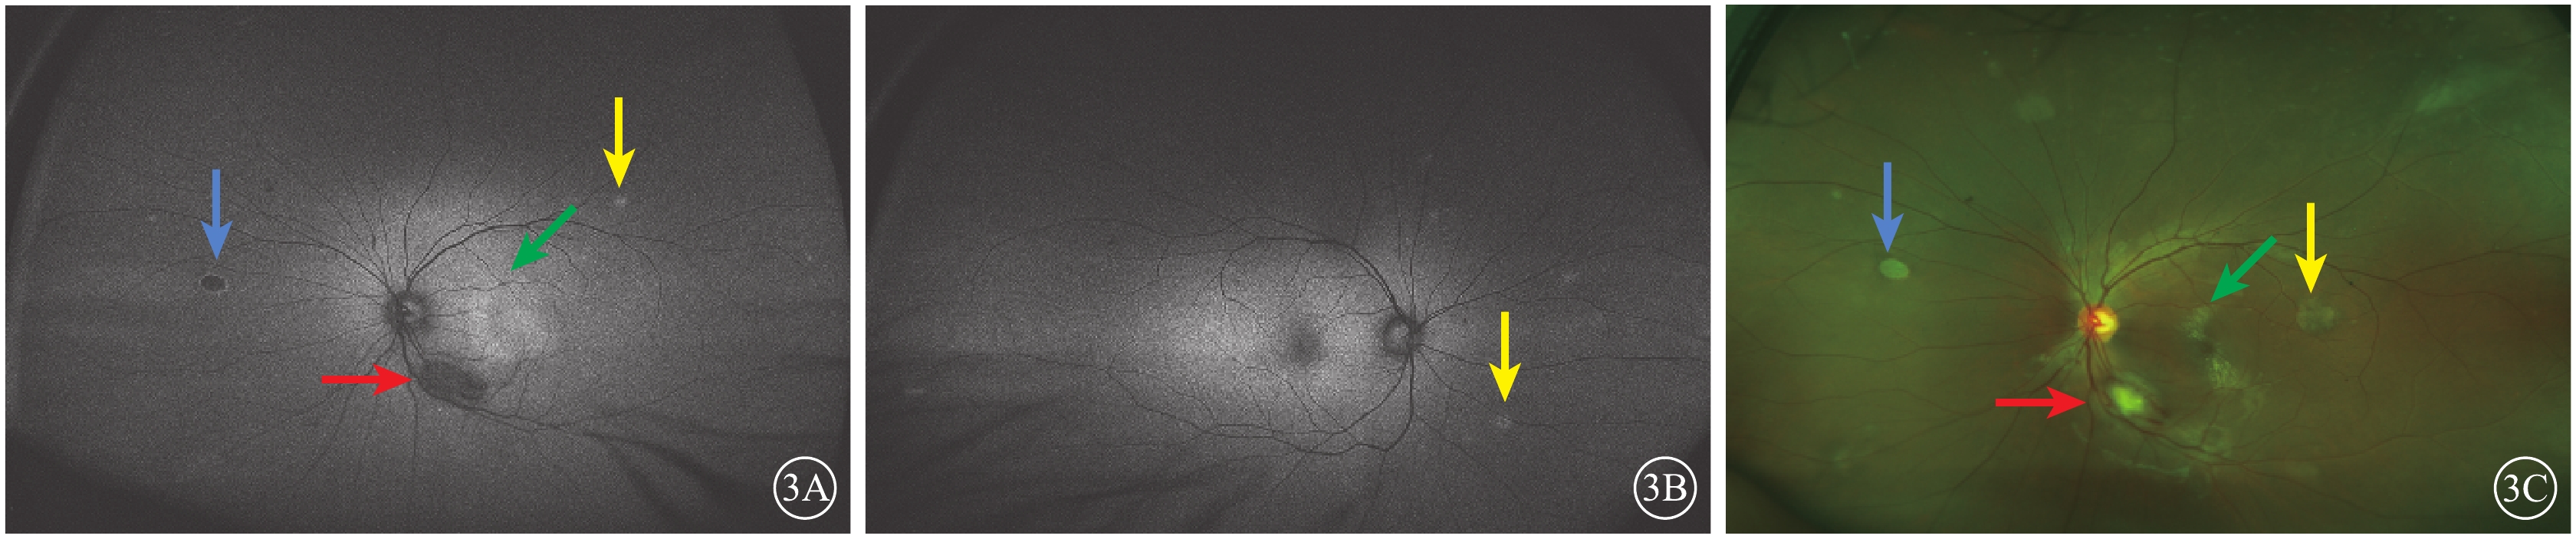

紅外眼底成像(IR)檢查,左眼視盤下方隆起病灶,結構紊亂,視盤上方可見兩處類橢圓形病灶(圖4A,4B)。光相干斷層掃描(OCT)血管成像(OCTA)檢查,左眼視盤下方病灶周邊部分可見血流,其余小病灶未見明顯異常(圖4,4D)。結合病史及輔助檢查,診斷為結節性硬化并發視網膜星形細胞錯構瘤。OCT檢查,左眼視盤下方視網膜光帶呈圓頂狀隆起,光帶增寬且反射增強,病灶內呈蟲蝕狀,各層結構不清,周圍視網膜層間水腫伴神經上皮脫離,其余各病灶對應區域OCT斷面上視網膜內層光帶增厚隆起,反射增強(圖5)。

圖5

患者左眼OCT像。5A.與圖4A對應病灶處視網膜內層光帶增厚隆起,反射增強(黃箭);5B.與圖4B對應病灶處可見隆起,結構紊亂

圖5

患者左眼OCT像。5A.與圖4A對應病灶處視網膜內層光帶增厚隆起,反射增強(黃箭);5B.與圖4B對應病灶處可見隆起,結構紊亂

紅外眼底成像(IR)檢查,左眼視盤下方隆起病灶,結構紊亂,視盤上方可見兩處類橢圓形病灶(圖4A,4B)。光相干斷層掃描(OCT)血管成像(OCTA)檢查,左眼視盤下方病灶周邊部分可見血流,其余小病灶未見明顯異常(圖4,4D)。結合病史及輔助檢查,診斷為結節性硬化并發視網膜星形細胞錯構瘤。OCT檢查,左眼視盤下方視網膜光帶呈圓頂狀隆起,光帶增寬且反射增強,病灶內呈蟲蝕狀,各層結構不清,周圍視網膜層間水腫伴神經上皮脫離,其余各病灶對應區域OCT斷面上視網膜內層光帶增厚隆起,反射增強(圖5)。

圖5

患者左眼OCT像。5A.與圖4A對應病灶處視網膜內層光帶增厚隆起,反射增強(黃箭);5B.與圖4B對應病灶處可見隆起,結構紊亂

圖5

患者左眼OCT像。5A.與圖4A對應病灶處視網膜內層光帶增厚隆起,反射增強(黃箭);5B.與圖4B對應病灶處可見隆起,結構紊亂